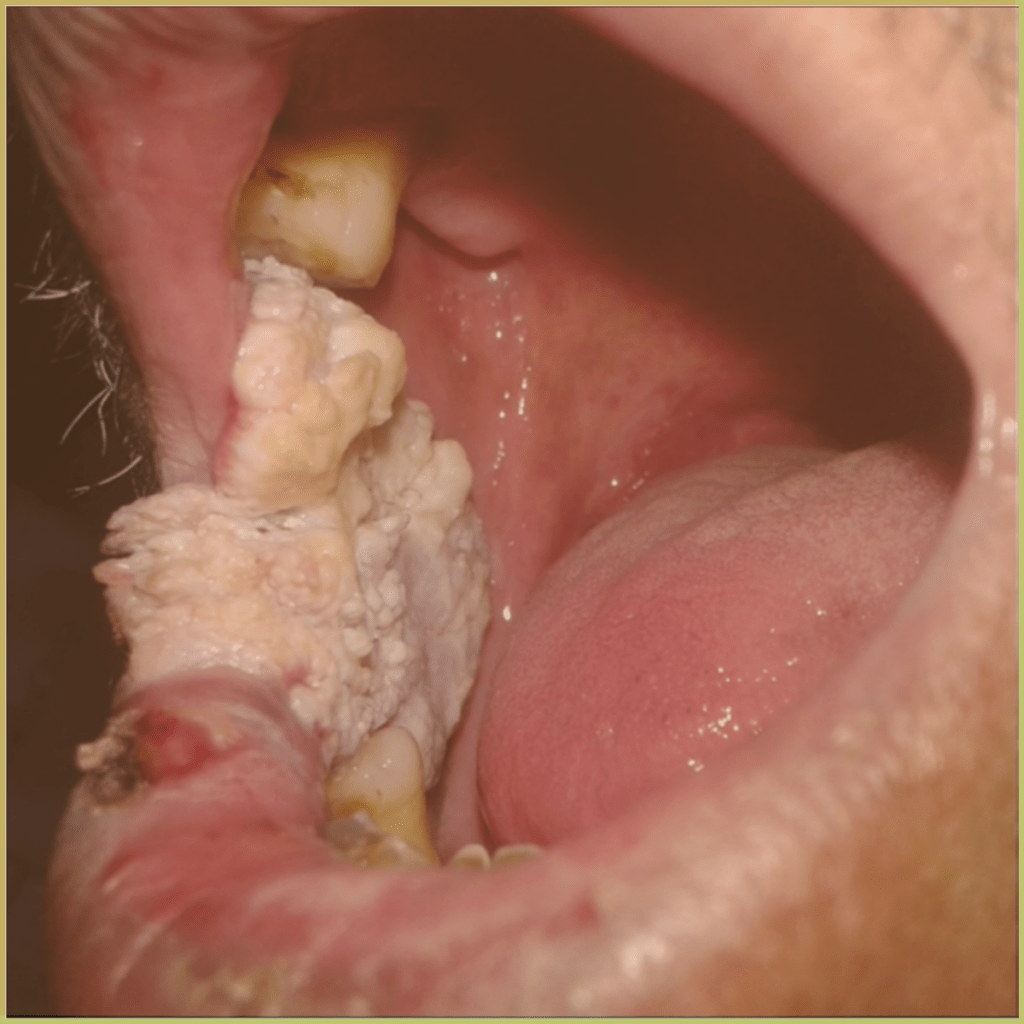

PROLIFERATIVE VERRUCOUS LEUKOPLAKIA (PVL)

Proliferative Verrucous Leukoplakia (PVL) is a rare but particularly aggressive clinical variant of oral leukoplakia. It is associated with a high probability of recurrence and a malignant transformation rate exceeding 70%. Tobacco use does not seem to have a significant influence on the appearance or progression of PVL, with the condition seen in both smokers and nonsmokers. There may be a link with human papillomavirus (HPV 16 and 18). The common clinical presentation includes:

- Slow progression and persistence.

- Early lesion – flat white plaque appearing as hyperkeratosis.

- Mature lesion – a multifocal, exophytic and proliferative lesion.

- Surface may be friable.

Diagnosis is based on the lesion history, clinical presentation and microscopic findings, which may include:

- Epithelial hyperplasia and hyperkeratosis.

- Atypical papillary-verrucal proliferation.

- Less differentiated oral squamous cell carcinoma.

Your differential diagnosis should include:

- Idiopathic leukoplakia.

- Oral warts or condyloma.

- Verrucous squamous cell carcinoma.

Treatment options include:

- Mucosal stripping or excision for immature lesions.

- Surgical excision with wide margins for advanced lesions.

- Laser ablation for benign or atypical lesions.

- Systemic retinoids to control keratosis.

Prognosis is poor for this seemingly harmless-appearing white lesion since it frequently progresses to carcinoma.